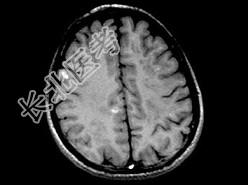

- 单项选择题男,26岁, 头痛、烦躁、意识障碍伴肢体活动障碍数天,头颅MRI检查见多发不规则小条片状结节状强化, 最可能的诊断是 ( )

A、脑结核

B、脑弓形虫病

C、化脓性脑炎

D、多发性硬化